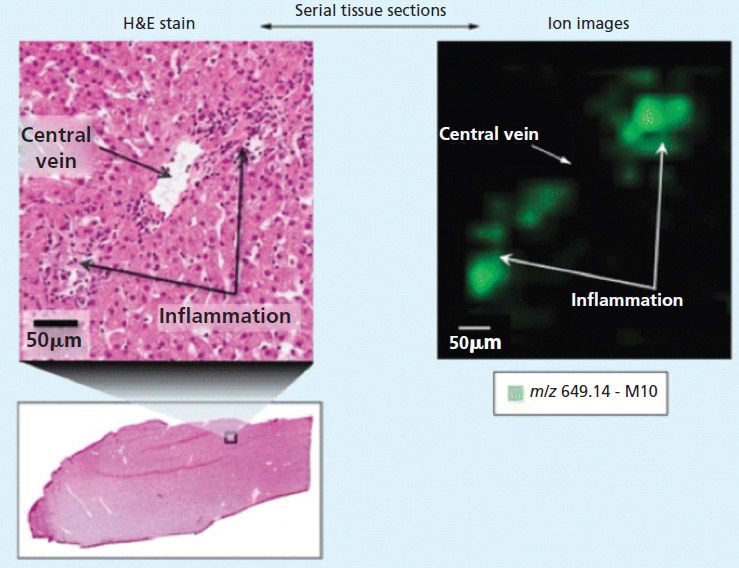

Against this background, MALDI imaging offers potential advantages for drug development. For example, MALDI imaging is generating important new information about the localization of drug compounds and important metabolites in tissue samples. Figure 1 shows an extract from an early work by Castellino and colleagues in which a small area of a histology section is magnified, showing regions of inflammation (3). An ion map (with 50-µm spatial resolution), which corresponds to the same region, indicates that the localization of lapatinib metabolite, M10, is only in the regions associated with the inflammation.

Figure 1: Correlation of histology and MALDI imaging in dog liver sections. Adapted with permission from reference 3.